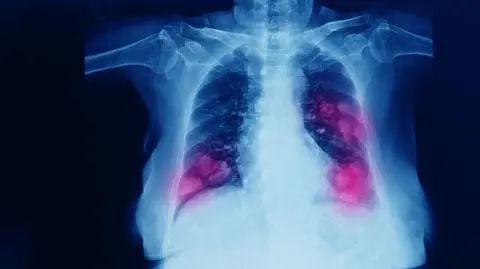

Jak zanieczyszczenie powietrza może prowadzić do raka płuc. "Cały ten mechanizm bardzo nas zaskoczył"